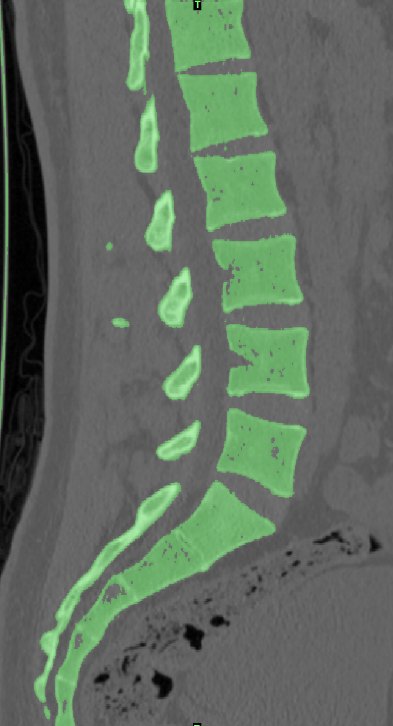

选取一名27岁青年男性志愿者在我院行腰椎螺旋CT扫描�����,扫描平面为���:第十二胸椎椎体至尾椎末端���,扫描厚度为0.625mm���,得到二维断层CT图像489张��,以DICOM格式进行储存���,导入计算机服务器�����。使用Mimics 19.0图像生成和编辑处理软件��,直接读取 DICOM格式的CT扫描数据进行三维重建���,见图 10����。根据软件中不同的灰度值来区分不同的组织����,用 Mimics 软件的阈值分割及区域增长功能画出腰椎(L3-5)����,不同的锥体用不同的颜色区分���,最后用图像填充功能填补图像中的空洞���,接着进行不同部位的三维重建��,得到仅包含骨性结构(L3-5)的模型��。将Mimics 软件得到的模型以STL格式模型文件导入Geomagic wrap2017软件中���,抹去模型钉状物和多余特征��,然后对模型进行优化光滑处理�����,将L3-5光滑处理后的每个锥体进行复制���,再将光滑后的模型在精确曲面中进行网格划分����,并进行构建曲面片及修理曲面片����,最后合成三维实体模型����,见图11�����。此时将复制的每个椎体模型外层向部件内部偏移2mm�����,内部充当松质骨��,外部的则定义为皮质骨����,椎弓根后部统一由皮质骨组成�����。随后将模型以STEP格式文件导入Solidworks2020软件中生成L3-5的实体模型零件��,并在模型零件中构建椎间盘��、髓核����、上下终板和软骨����,完成的实体模型���,此时的模型为单纯的正常腰椎三维几何模型���,各结构并未赋予材料属性与网格划分����,见图12�����。将模型导入ANSYS软件中���,随后对模型中皮质骨���、松质骨���、软骨����、终板���、纤维环���、髓核赋予相应的材料属性赋值���,尽可能地还原各组织材料的生理状况�����,提高模型的可靠性���。定义关节突关节面为 Frictional����,摩擦系数设为0.1��。在connections中建立spring模块���,模拟前纵韧带����、后纵韧带���、黄韧带��、棘间韧带���、棘后韧带���、横突间韧带及关节囊韧带��,各韧带对应刚度赋值��。建立完成后�����,对模型进行mesh操作构建网格���,见图13����。

图 10 Mimics 图 11 Geomagic